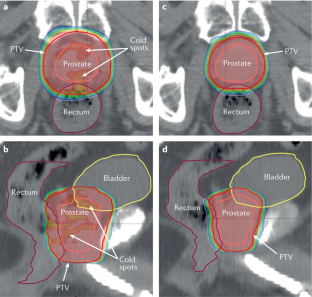

Heemsbergen, W. D. et al. Increased risk of biochemical and clinical failure for prostate patients with a large rectum at radiotherapy planning: results from the Dutch trial of 68 GY versus 78 Gy. Int. J. Radiat. Oncol. Biol. Phys. 67, 1418–1424 (2007).

De Crevoisier, R. et al. Increased risk of biochemical and local failure in patients with distended rectum on the planning CT for prostate cancer radiotherapy. Int. J. Radiat. Oncol. Biol. Phys. 62, 965–973 (2005).

Moiseenko, V., Liu, M., Kristensen, S., Gelowitz, G. & Berthelet, E. Effect of bladder filling on doses to prostate and organs at risk: a treatment planning study. J. Appl. Clin. Med. Phys. 8, 55–68 (2006).